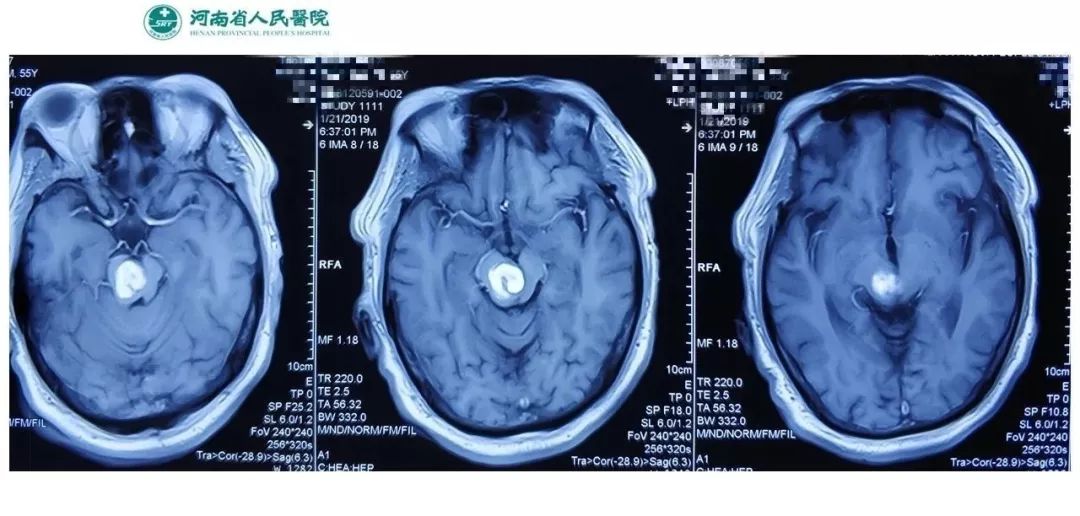

术前影像:透明隔腔明显增宽,双侧脑室、三脑室、脚间池明显扩张、积水,周围脑实质受压,胼胝体受压变薄。弥散加权图像未见异常。中线结构居中。增强扫描未见异常强化。

术前诊断:三脑室内囊肿,幕上脑积水。

脑室内蛛网膜囊肿多位于侧脑室和第三脑室内;CT值10HU以下或MRI信号等同CSF;囊肿圆形或椭圆形,边缘光滑,壁薄,无结节;脑室扩大变形,周围无水肿。侧脑室囊肿多位于侧脑室三角区,蒂部位于室间孔周围。第三脑室囊肿常位于第三脑室前上方,室间孔开口处,一旦阻塞可引起一系列的临床症状,如头痛、头晕和呕吐等。